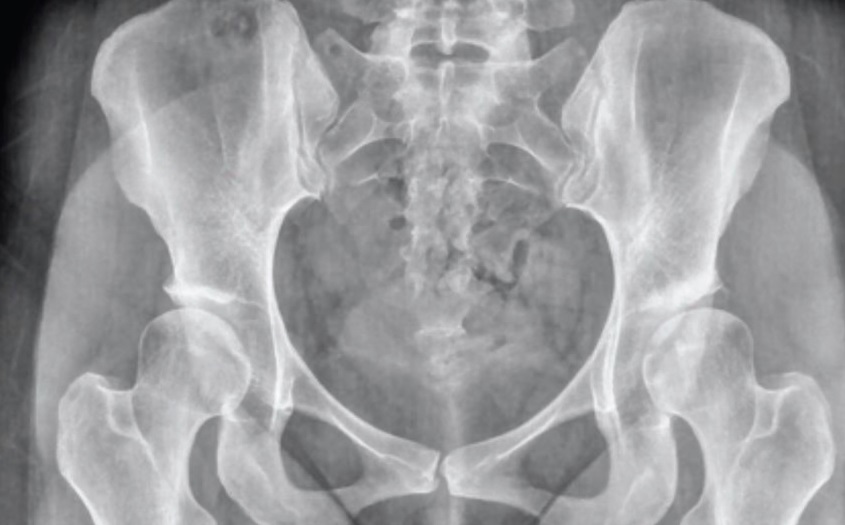

Kalça Osteoartriti

Devamı